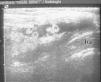

La radiografía mostraba una masa de partes blandas en la fosa antecubital, sin signos evidentes de osteoartritis del codo. En la ecografía se evidenció una masa de ecoestructura mixta, con zonas de contenido líquido anecoico y otras áreas hiperecógenas en las que se sospechaba la presencia de grasa (fig. 1). Se practicó una resonancia magnética (RM) (General Electric, 1.5T) con una antena de superficie de extremidad y se realizaron secuencias sagital fast spin-echo (FSE) T2 supresión grasa y axiales FSE T1, FSE T2 supresión grasa y FSE T1 supresión grasa tras la administración de contraste (gadolinio quelado a dietilenotriamino pentaacético [Gd-DTPA]). Se identificó una masa circunscrita que se extendía a lo largo de la bursa bicipitorradial del codo y rodeaba el tendón del bíceps, con una señal heterogénea a expensas de un componente de tipo fluido correspondiente a derrame en la bursa y focos de tejido graso como pequeñas formaciones polipoides desde la pared hacia el interior de la tumoración. Tras la administración de contraste se evidenció un realce importante de la pared de la masa y de sus proliferaciones (fig. 2).

Resonancia magnética. Masa que rodea parcialmente a la porción distal del tendón bicipital (t.b.) en la que se observan las proliferaciones grasas vellositarias isointensas con la señal del tejido celular subcutáneo. La orientación de la imagen sagital equivale aproximadamente a la imagen ecográfica de la figura 1. A) Imagen sagital FSE T2 con supresión grasa. B) Imagen axial FSE T1. C) Imagen axial FSE T1 con contraste. FSE: fast spin-echo 'eco spin rápido'.